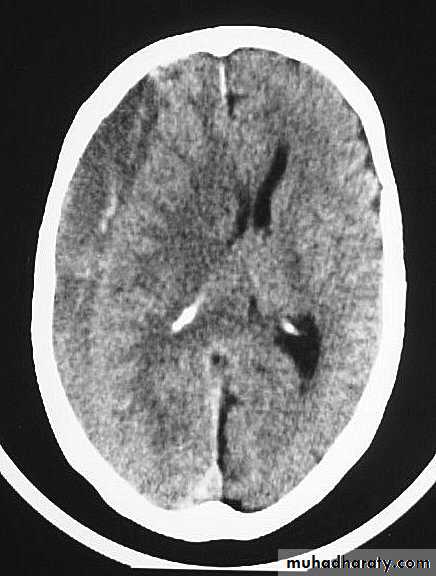

5. Hydrocephalus

a. Acutely due to obstruction of CSF outflow due to intraventricular blood.

b. Delayed post-traumatic communicating hydrocephalus due to impaired CSF reabsorption following traumatic subarachnoid haemorrhage

Intraventricular blood can lead to Hydrocephalus